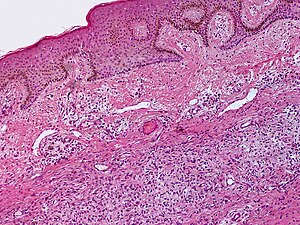

Dermatofibroma. H&E stain. | |

| LM | prominent fibrous bundles - especially at the edge of the lesion ("collagen-trapping"), loss of adnexal structures, +/-"dirty fingers" (acanthosis, basal keratinocyte hyperpigmentation) |

Features:[3]

- Prominent fibrous bundles, especially at the edge of the lesion.

- Surrounded by spindle cells (fibroblasts).

- Usually thought of as fibroblasts surrounded by fibrous material ("collagen-trapping").

- Lack of adnexal structures, i.e. no sweat glands, no hair.

- +/-Epidermal changes - known as "dirty fingers":[4]

- Acanthosis (thickened epithelial layer - specifically thickened stratum spinosum).

- Basal keratinocyte hyperpigmentation.

The sections show skin with bland spindle cells interspersed between fibrous bundles. The fibrous bundles are prominent at the periphery of the lesion (collagen-trapping). Focal acanthosis is present.

The lesion does not extend to the adipose tissue. No atypia is apparent. No mitotic activity is identified.